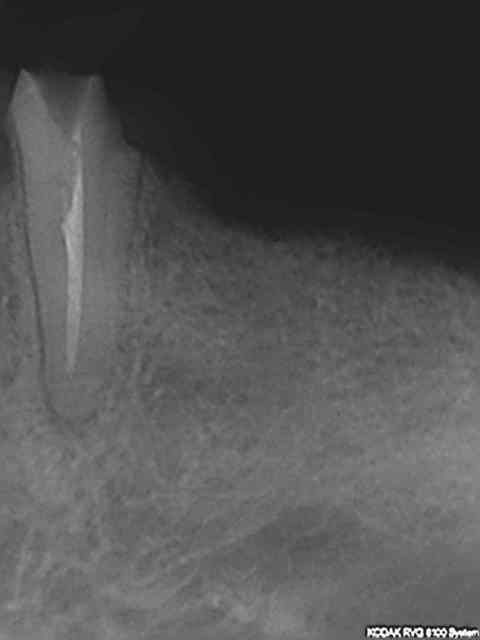

J'utilise d'autres cones je ne sais plus quelle marque mais plus fermes il est vrai. Presque toutes mes endos ressemblent à ca, autant que faire ce peu à mon niveau j'ai trouvé une séquence qui permet d'avoir des résultats reproductibles. Presque car j'ai quelques ratés aussi Genre un instrument de cassé de temps en temps, jamais de fausses routes cependant.

La toile rte du mois quelques fractures instrumentales sur le mv1 (1 puis 2 puis 3) et mv2 récalcitrant.

R2 uvhruy - Eugenol